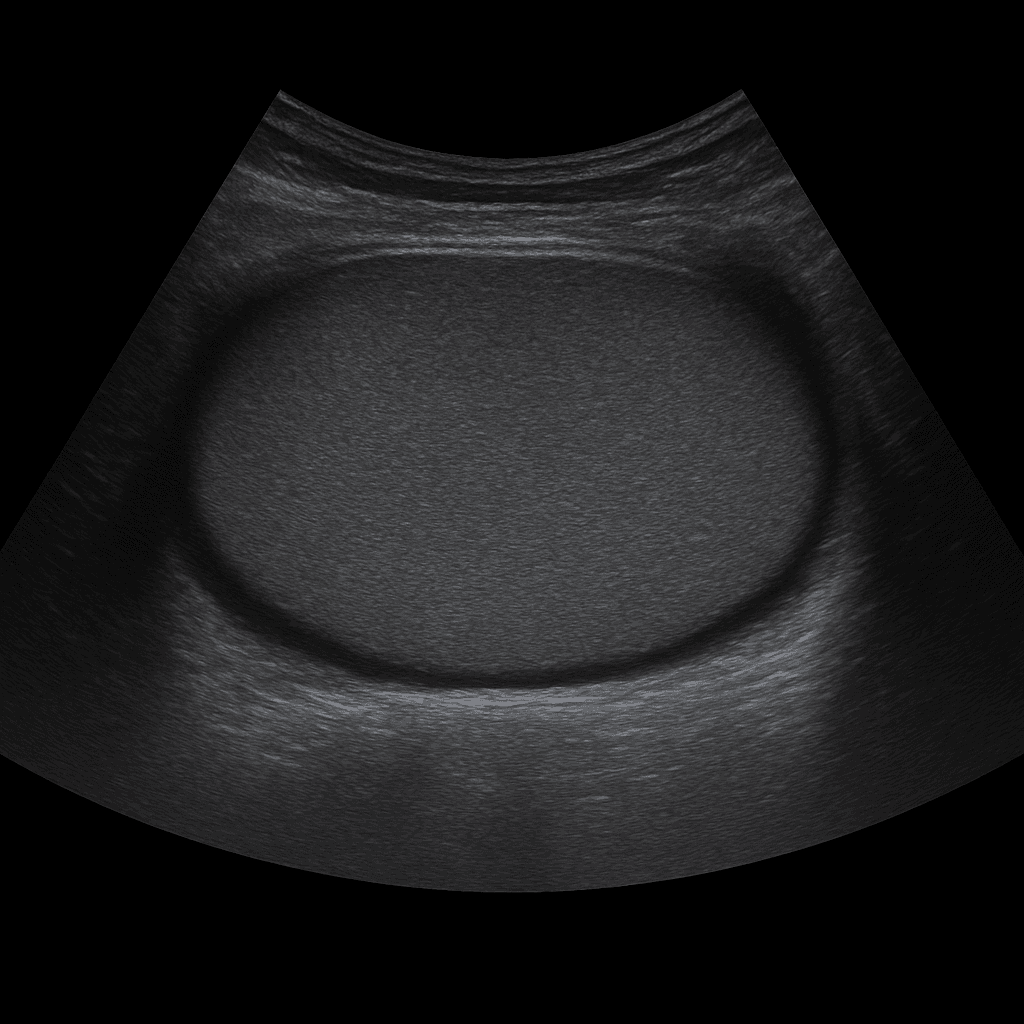

Ett ultraljud av testiklar används för att undersöka testiklar, bitestiklar och omgivande vävnader i pungen. Undersökningen utförs av specialistläkare inom radiologi och ger detaljerade bilder i realtid som kan visa inflammation, vätskeansamling, cystor, blodcirkulation och eventuella tumörförändringar. Ultraljud testiklar är den vanligaste metoden vid smärta, svullnad eller knöl i pungen.

Undersökningen utförs när du ligger på rygg. En gel appliceras på huden och läkaren för ultraljudsproben över pungen för att bedöma testiklar och bitestiklar i detalj. Undersökningen tar cirka 10–15 minuter, är helt smärtfri och kräver ingen särskild förberedelse. Vid behov kan blodflödet studeras med dopplerteknik för att upptäcka vridningar eller cirkulationspåverkan.